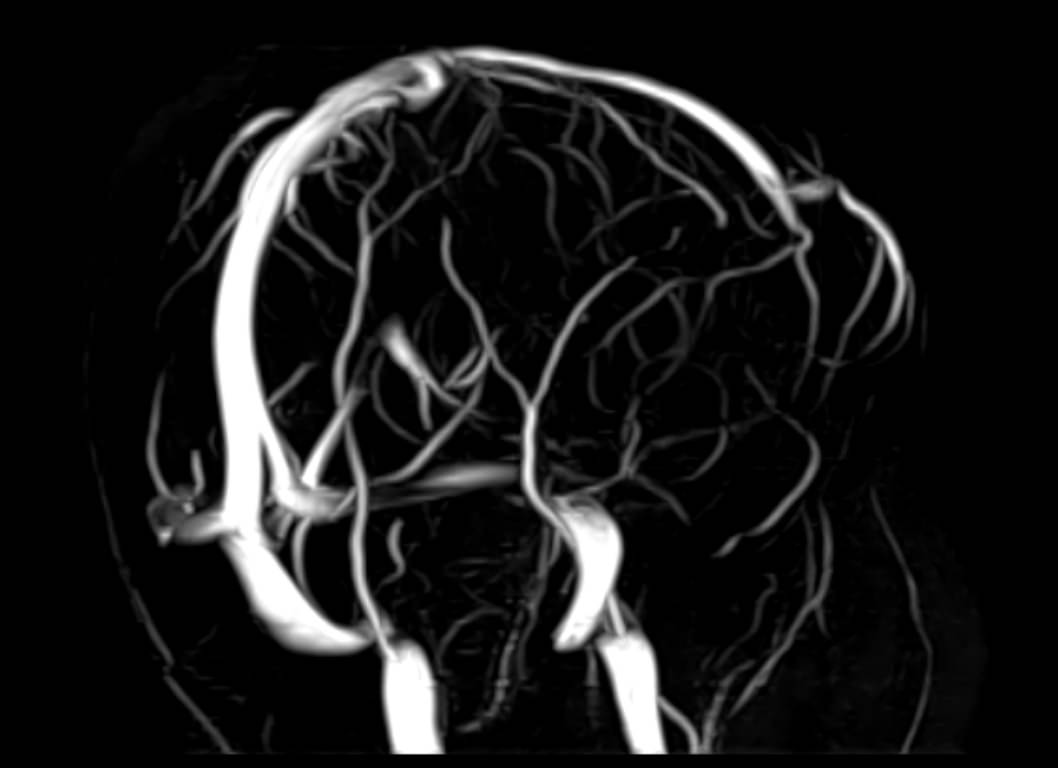

МРТ головного мозга является высокоинформативным методом исследования центральной нервной системы, который дает возможность оценить состояние всех структур головного мозга и поставить правильный диагноз. Стандартную МРТ головного мозга дополняет МР-венография, которая позволяет получить детальную картину строения и функционального состояния венозной системы мозга.

В клинике «Доступная медицина» проводится МРТ головного мозга и МР-венография головного мозга на современном аппарате TOSHIBA VANTAGE TITAN 1,5 Тесла, который обладает высокой чувствительностью и соответствует всем мировым стандартам качества диагностики. Напряженность магнитного поля 1,5 Тесла обеспечивает высокую четкость изображения и позволяет выявлять заболевания на ранних стадиях развития. Процедура МРТ безопасна, так как томограф не испускает рентгеновского излучения, полностью безболезненна и имеет доступную стоимость.

• участки сужения, извитость, образование петель и перегибов сосудов;

• нарушения оттока крови за счет тромбообразования в венозном русле;

• ангиомы, сосудистые мальформации.